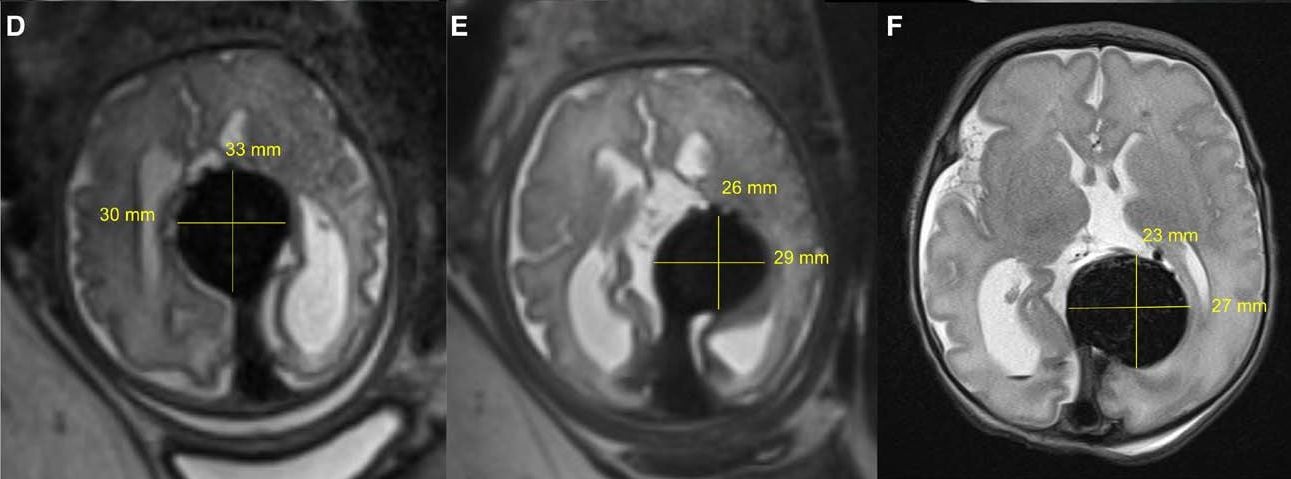

Malformacja żyły Galena (VOGM) to rzadki stan prenatalny, który wynika z nieprawidłowego rozwoju żyły wielkiej mózgu (żyły Galena). Tętnice doprowadzające krew z serca do mózgu łączą się bezpośrednio z żyłami, a nie naczyniami włosowatymi, które w przeciwnym razie kontrolowałyby przepływ krwi. Oznacza to, że krew może wywierać ogromne nacisk na serce i płuca, zwłaszcza u noworodka, po porodzie. To prowadzi do nadciśnienia płucnego, niewydolności serca lub innych stanów zagrażających życiu. VOGM jest najczęściej po raz pierwszy obserwowany na USG prenatalnym i ostatecznie diagnozowany przez MRI pod koniec drugiego lub trzeciego trymestru ciąży.

Amerykańscy chirurdzy przeprowadzili udaną wewnątrzmaciczną embolizację płodu z VOGM w 34. tygodniu i drugim dniu ciąży. To pierwsza taka operacja in utero na świecie.

Echokardiografia po urodzeniu wykazała postępującą normalizację pojemności minutowej serca. W opisywanym przypadku noworodek nie wymagał żadnego wspomagania układu krążenia ani operacji po leczeniu wewnątrzmacicznym i był na obserwacji na OIOM-ie przez kilka tygodni po urodzeniu z powodu wcześniactwa. Wszelkie badania wskazują, że dziecko rozwija się prawidłowo.